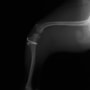

■ 症例22 ポメラニアン 1歳5か月 去勢雄

左後肢の挙上を主訴に来院した。整形学的検査、レントゲン検査より左右の膝蓋骨脱臼(左GradeⅡ〜Ⅲ、右Grade Ⅱ)を認めた。また、脛骨の前方引き出し試験の際に、引き出し兆候は認められないものの、疼痛が認められたため、前十字靭帯の損傷が疑われた。術中における、目視および関節内の操作によって、前十字靭帯の損傷や過伸展といった異常が認められなかったため、膝蓋骨脱臼の整復のみ実施した。手術手技は縫工筋及び内側広筋の解放、脛骨粗面の外側転位、滑車ブロック形造溝術、内外側関節包の縫縮を実施した。本症例は跛行もなく経過良好である。しかし、頸骨高平部の角度(TPA)が 右26.2°、左24.9°であり、解剖学的に前十字靭帯損傷のリスクが高いことから今後の経過に注意が必要である。